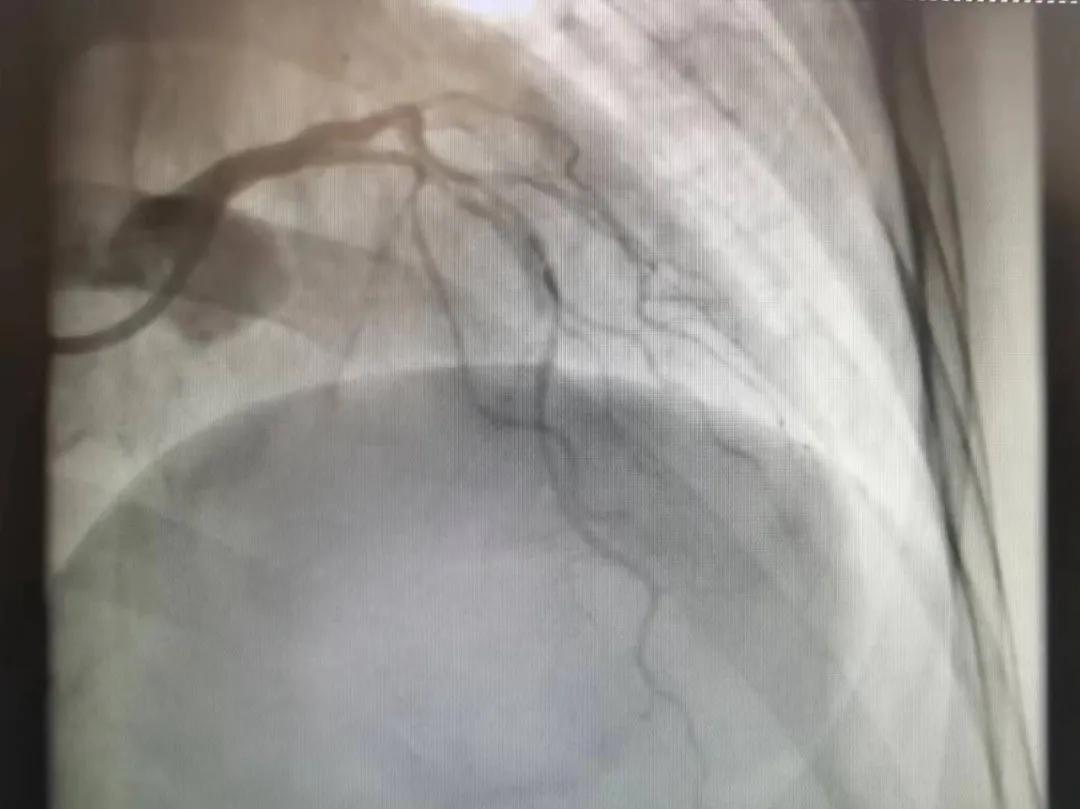

病人是位六十多歲的女性患者,有長期高血壓病史,1個月前開始出現(xiàn)胸悶胸痛,口服藥物治療效果不佳,經(jīng)朋友介紹,來到市二院心血管內(nèi)科。入院后完善冠狀動脈造影提示:前降支全程彌漫性狹窄伴鈣化,最重95%,回旋支狹窄約85%,右冠脈全程狹窄伴鈣化,最重60%。血管內(nèi)超聲顯示右冠脈開口面積3.36mm²,可見環(huán)形鈣化,考慮患者病變程度重、鈣化明顯,常規(guī)器械無法實現(xiàn)病變的良好預(yù)處理,且有很高的冠脈穿孔、血管夾層的風(fēng)險。

術(shù)前

王瑾院長和李慧新主任帶領(lǐng)介入團(tuán)隊充分評估,決定行前降支冠狀動脈鈣化病變旋磨術(shù),術(shù)中應(yīng)用1.5mm旋磨頭,以15萬-17萬轉(zhuǎn)/分速度共對病變旋磨3次,累計旋磨時間60秒,后復(fù)查造影示鈣化明顯減輕,為后續(xù)操作創(chuàng)造了良好條件,隨后應(yīng)用預(yù)擴(kuò)張球囊、切割球囊再次處理病變,并順利植入支架1枚,復(fù)查造影顯示支架膨脹及貼壁良好,無夾層、血腫、慢血流等情況,手術(shù)順利完成?;颊咝g(shù)后無不適,胸悶、胸痛癥狀明顯緩解,順利出院。

術(shù)后